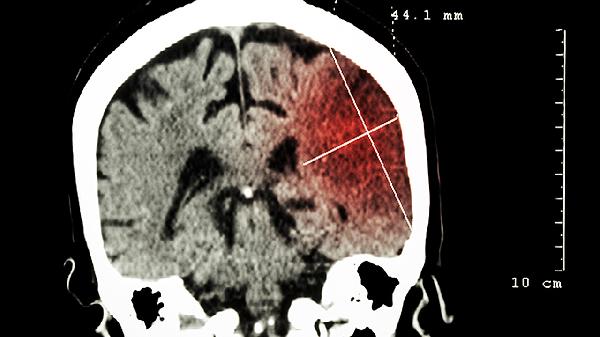

脑供血不足导致缺氧该吃什么药有效

对于脑供血不足引起的缺氧情况,应在医生指导下使用阿司匹林肠溶片、尼莫地平片、盐酸氟桂利嗪胶囊、银杏叶片以及胞磷胆碱钠片等药物。这种状况可能与动脉硬化、颈椎问题等相关,常见症状包括头晕和视力模糊。建议尽快就医,并在专业医生的指导下进行规范治疗。